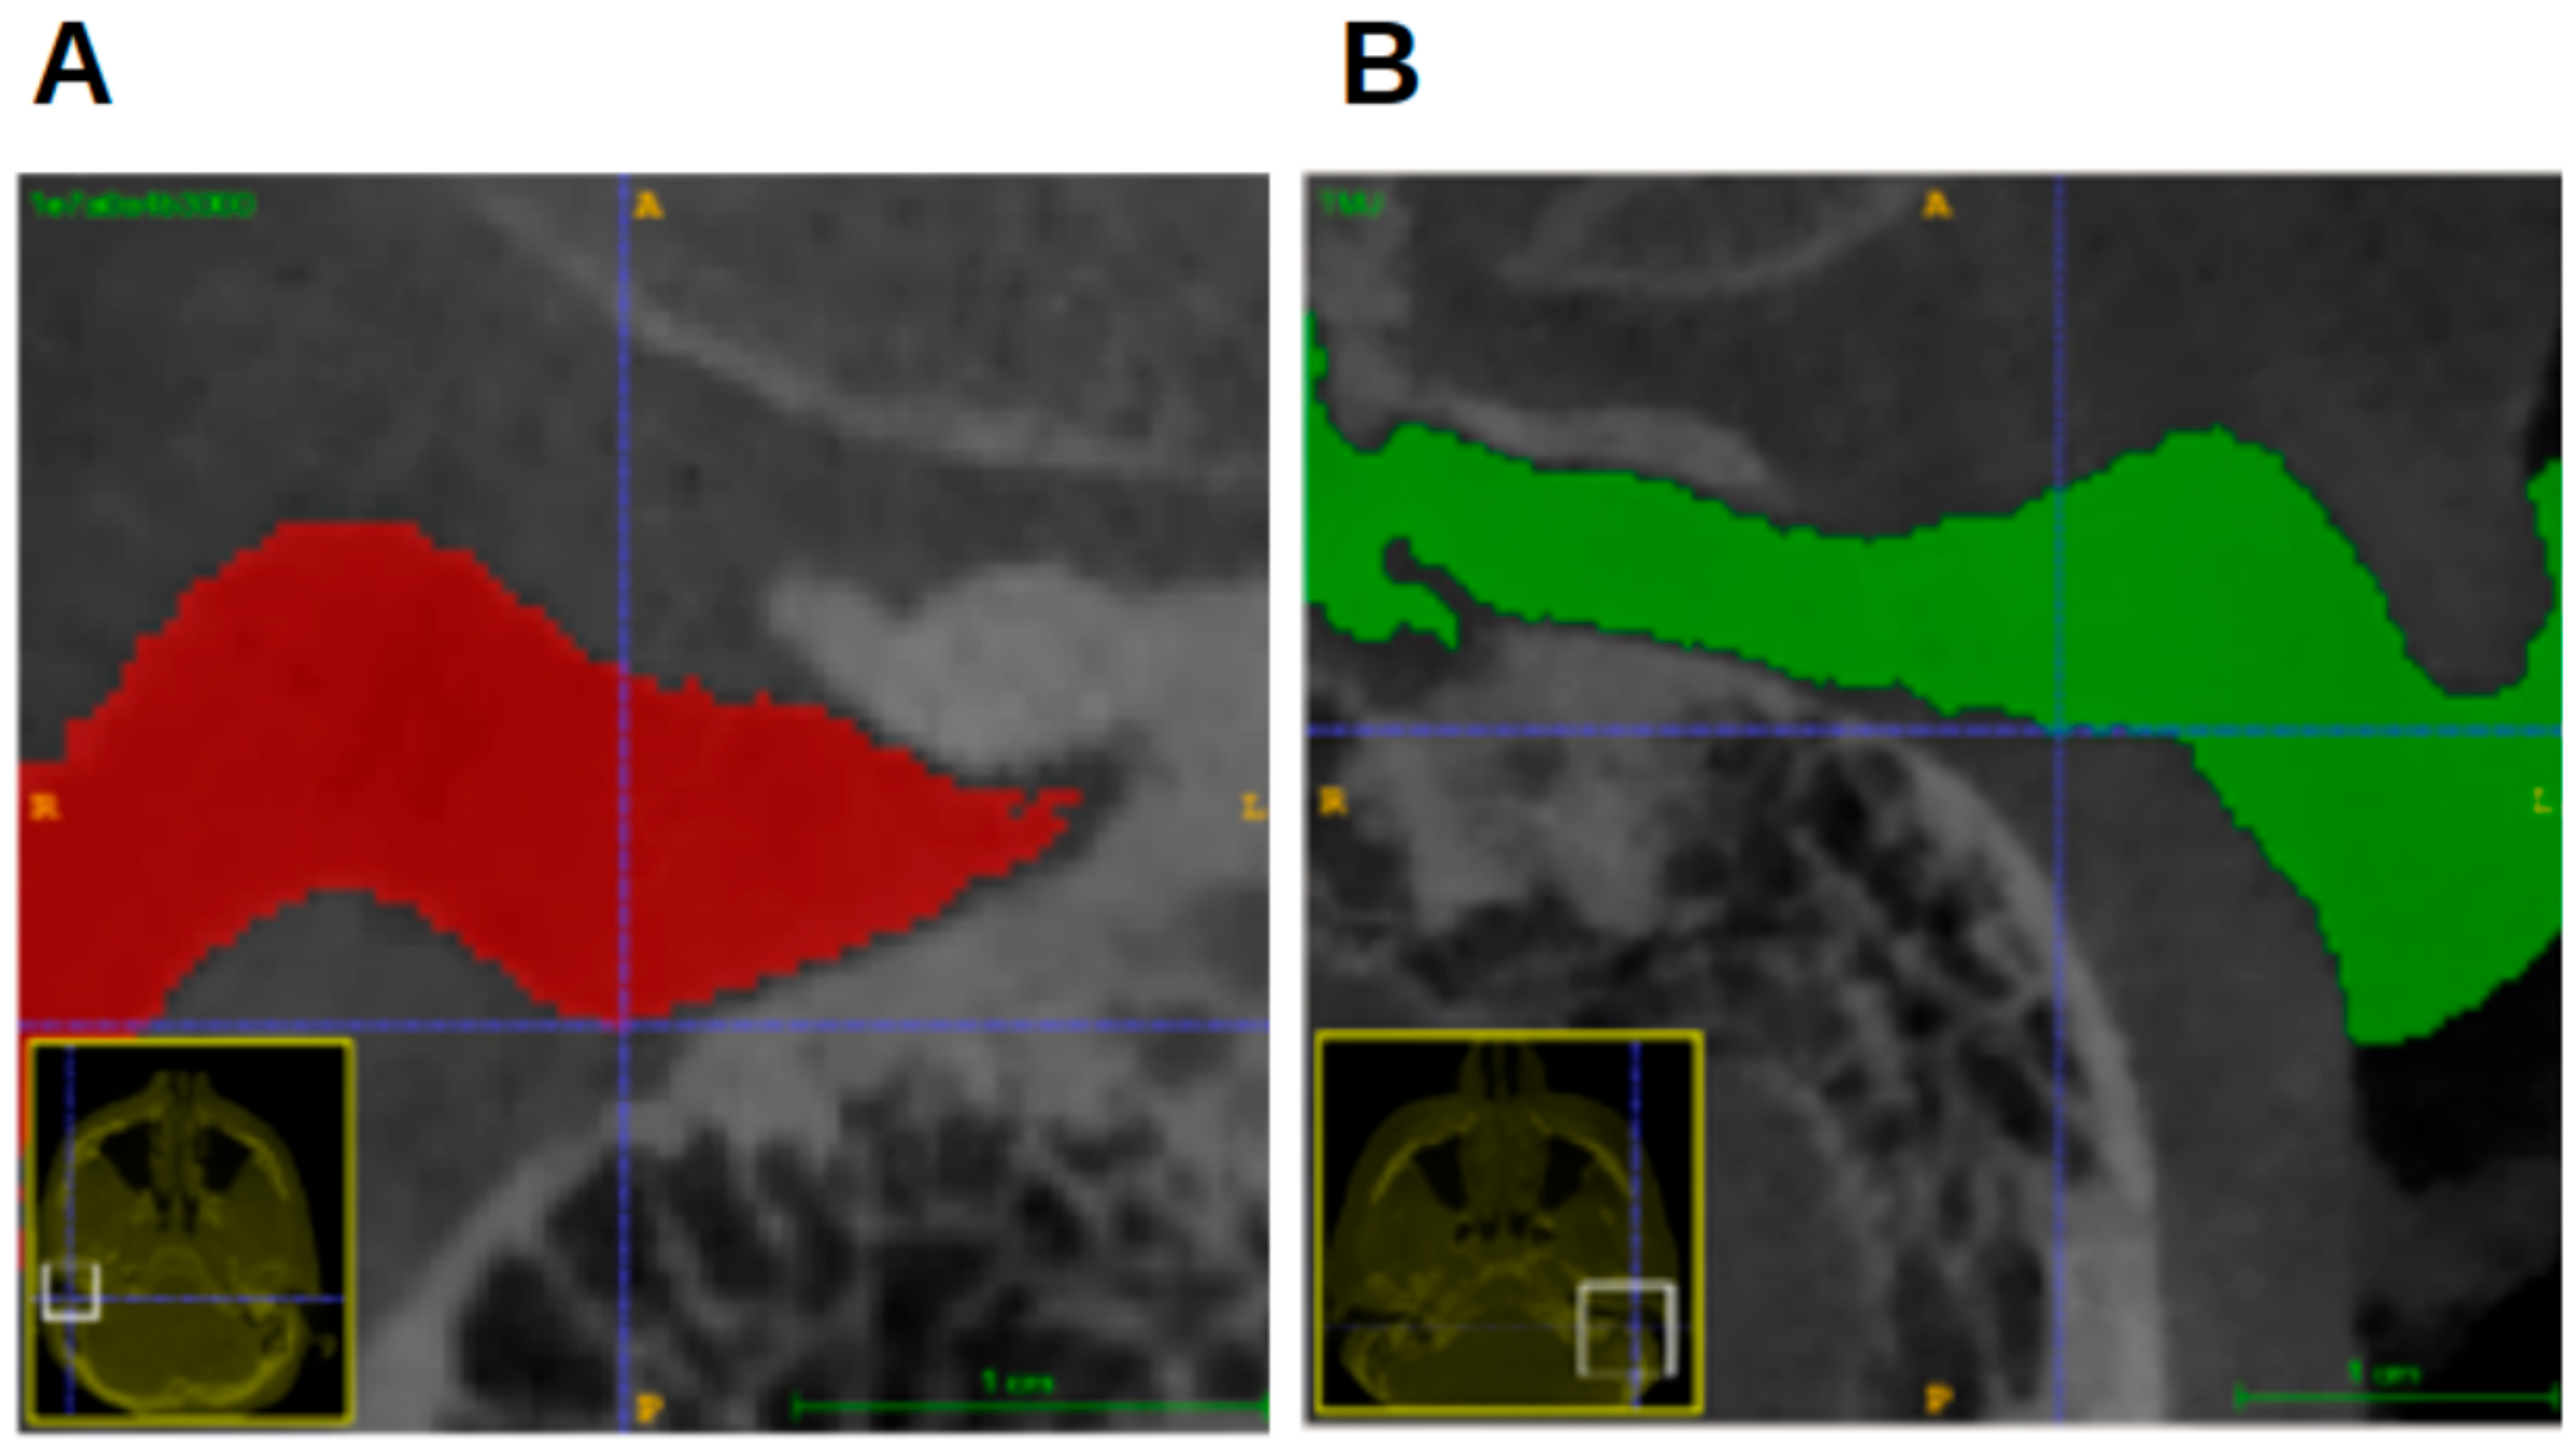

Although the most superior point is often used as a definition for the Porion or as a landmark in the EAM, its location was set differently in this study (Figure 9), using the most superior point in the coordinate system of the segmentation.

Figure 9. Location of most superior point. (A) CBCT image in coronal view. Blue crosshairs: most superior point. (B) Green circle: location of most superior point of EAM according to some studies. (C) Schematic image (“MedicalGraphics–Drawing Ear anatomy–no labels” at AnatomyTOOL.org by www.MedicalGraphics.de; license: Creative Commons Attribution-NoDerivatives). Green circle: location of most superior point of EAM according to some studies. Blue arrow: location of most superior point according to present study.